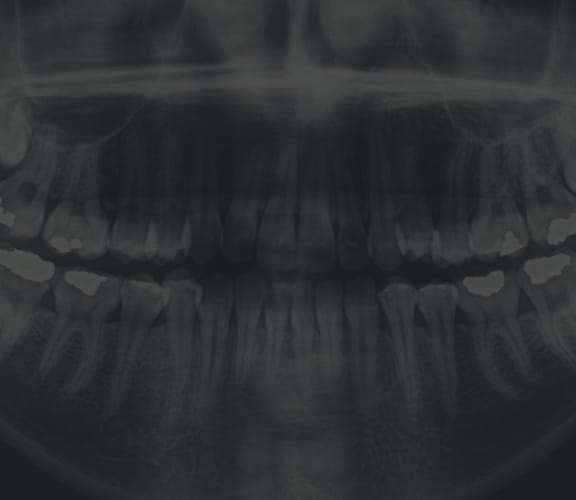

Crown lengthening is a surgical procedure that re-contours the gum tissue and often the underlying bone of a tooth. Crown lengthening is often for a tooth to be fitted with a crown. It provides necessary space between the supporting bone and crown, which prevents the new crown from damaging bone and gum tissue.